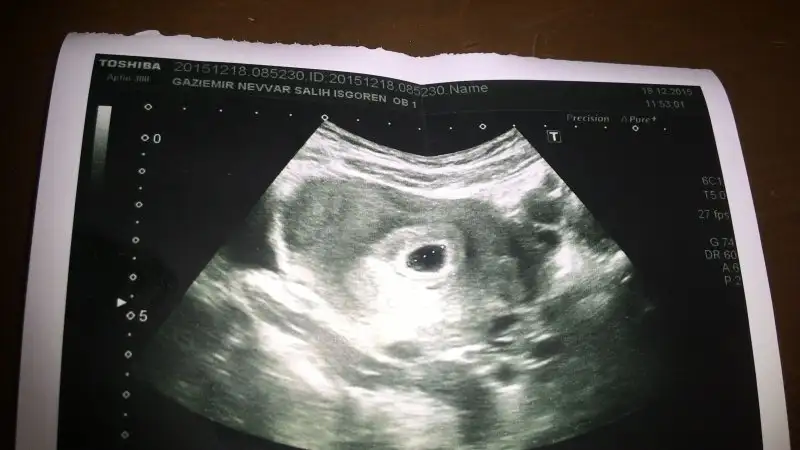

Ilk eklediğim 6 haftalik ama. Dr bebek yok icinde demisti. Ikincisi 8 haftalik

Bu yolk kesesi falan yazmissin cnm yolk ve plesanta zit yondemi olmasi gerekio

6. Haftada öyle oluyor ama ileriki haftalarda özellikle 8+lardan itibaren sanırım bebek de dönmeye başlıyor. Bir de yolk sac küçülüyor o zaman ayak ucuna doğru kayıyor yolk sac tahmin de zorlasiyor... en dogru 6+larda belli oluyor. Birde ilk plesantanin yerlestigi nokta onemli mesela benim 6+2 de vajinal olarak plesanta sag yerleskeliydi... 9+0 da gene vajinal bakil bu sefer plesanta buyumus ve kapladigi alan da haliyle genislemis ve sanki kesenin tepesini kapliyor gibiydi... yani 8. Haftadan sonra tahmin yapilmasi güç...